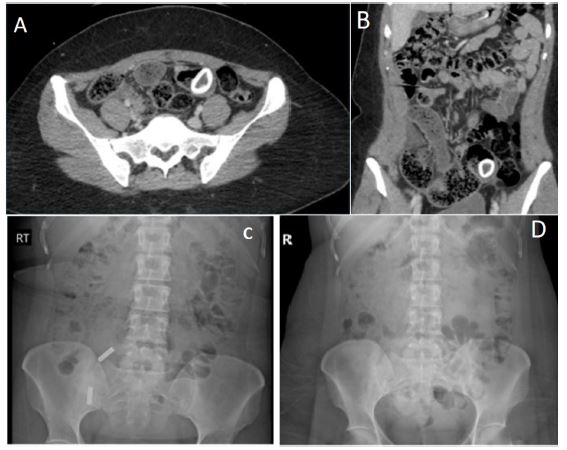

After one day, the patient’s condition had not improved, and she had not had a bowel movement. To assess the status of the foreign body and determine if it was visible and in transit compared to the previous CT scan, an abdominal X-ray was obtained. An X-ray performed the previous evening did not reveal any foreign body (Figure 1).

Figure 1: (A) Axial view of the CT Abdomen/Pelvis with IV contrast done the day of admission showing dilated distal small bowel loops and a ring-shaped high density in the mid to distal small bowel. No clear transition point is seen. (B) Coronal view of the CT Abdomen Pelvis with IV contrast done the day of admission showing dilated distal small bowel loops and a ring-shaped high density in the mid to distal small bowel. No clear transition point is seen. (C) Abdominal X-ray from the day of presentation showing nonspecific bowel gas patter and moderate diffuse constipation. Two radiopaque foreign bodies in RLQ were seen which were artifacts caused by objects from the outside. (D) Repeat abdominal X-ray one day after presentation showing unchanged bowel gas pattern and mild stool burden. Foreign body seen on CT scan is not visible on the X-ray.